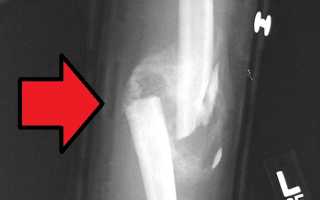

При переломе кости происходит сращение обломков с образованием новой ткани, известной как костная мозоль.

- Периостальная мозоль. Этот тип мозоли проявляется в виде небольшого утолщения вдоль линии перелома кости.

- Эндоостальная мозоль. Данная костная мозоль образуется внутри самой кости. У некоторых пациентов может наблюдаться незначительное уменьшение толщины костной ткани в области перелома.

- Интермедиальная мозоль. В этом случае костная мозоль располагается между фрагментами кости, при этом профиль кости остается практически неизменным.

- Параоссальная мозоль. Она образует широкий выступ вокруг поврежденной части кости. На рентгеновских снимках этот выступ может искажать как форму, так и структуру сломанной кости.

Тип костной мозоли, который возникнет у человека после перелома, зависит от его регенеративных способностей, а также от локализации повреждения или перелома.